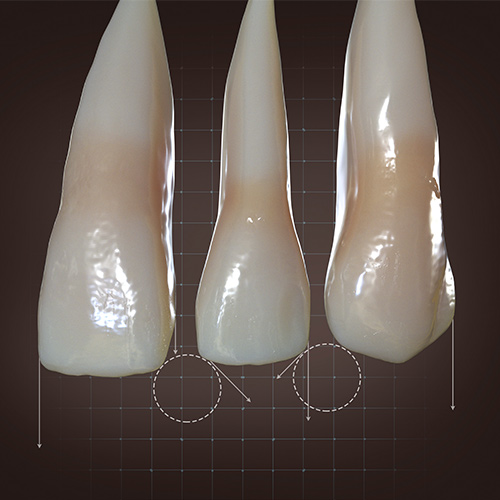

Early Diagnosis and Treatment of Asymptomatic Vertical Enamel and Dentin Cracks

Samer S. Alassaad, DDS

Wednesday, November 23, 2022

This Compendium eBook offers a continuing education (CE) article that presents a systematic approach for the early diagnosis and treatment of asymptomatic vertical enamel and dentin cracks based on current evidence. Download to earn 2 FREE CEU now!

Current Topics in Restorative Dentistry

Monday, February 26, 2018

This Compendium eBook provides two continuing education articles on restorative dentistry, each focusing on topics related specifically to enamel. In the first CE, the author offers a systematic approach for early intervention for asymptomatic vertical enamel and dentin cracks based on current evide...